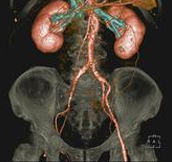

Body angiography with automatic table removal ? colored volume rendering reconstruction. Case: Aortic dissection. Left common iliac artery occlusion. Scanning: P0.83, 0.5s, 360mA, 100kV, weight 80kg, contrast 80cc

Save split image 2 x (512 x 512) matrix possible to see high resolution 3D image without doing partial reconstruction.

Save split image 2x(512 x 512) matrix possible to see high resolution 3D image without doing partial reconstruction.